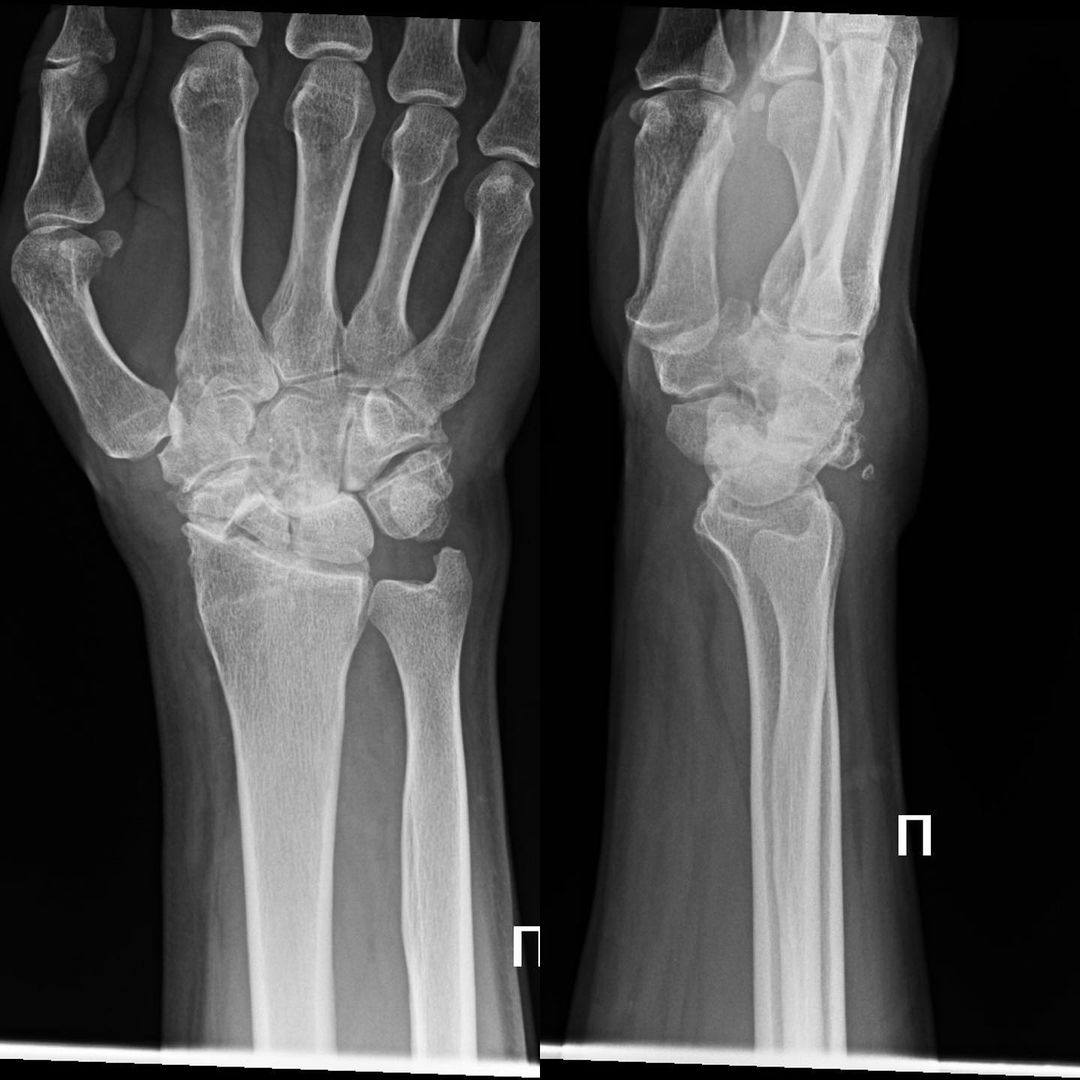

Пациент обратился к Гайку Кареновичу с жалобой на боль и ограничение подвижности в лучезапястном суставе.

Анамнез: около 15 лет назад получена травма – перелом, про который пациент знал, но не лечил руку.

• Из-за нарушения положения костей, в запястье развился артроз, который еще больше нарушил положение костей. Цикл неоднократно повторялся, и с каждым новым витком проблема усугублялась.

• Функция кисти пострадала, что привело к болезненности и ограниченности движений.

Это не единичный случай – многие люди годами живут с несросшимся переломом ладьевидной кости, который плавно переходит в ложный сустав, из которого еще плавнее вытекает артроз во всем лучезапястном суставе!